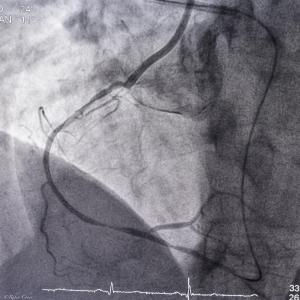

CTO Case 2017 Carmel Hospital Israel